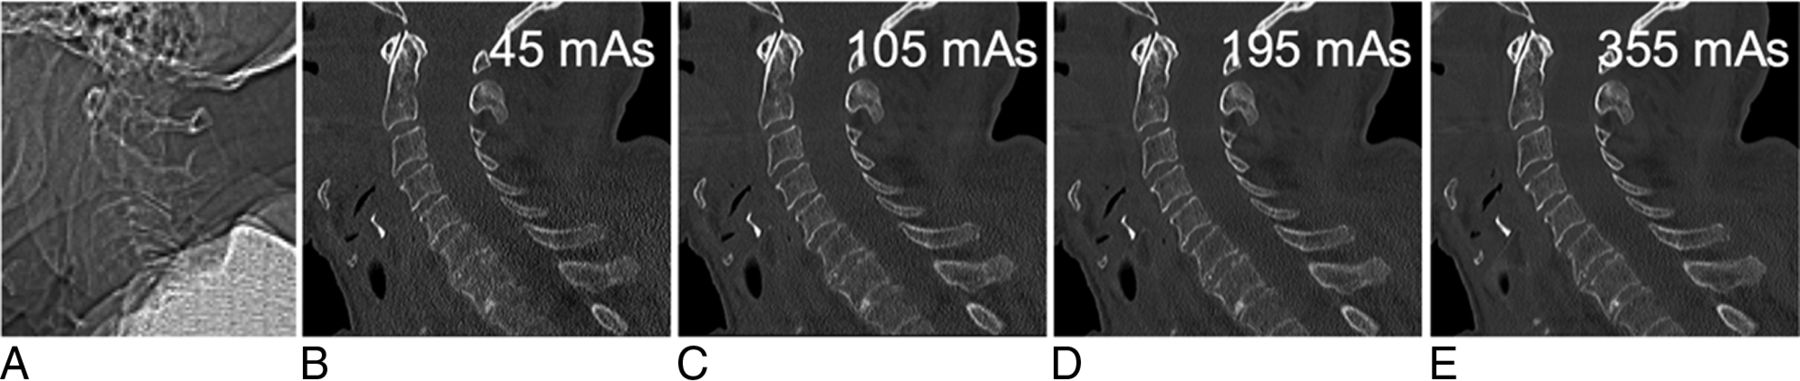

Lateral topogram (A) of this cadaveric specimen reveals shoulder height at the C5 level. Sagittal reformatted CT images (B–E; window level/width, 600/2000) of the cervical spine at 45, 105, 195, and 355 mAs reconstructed with sonogram-affirmed iterative reconstruction (strength level, 3) using bone convolution kernels show a decreasing image noise with increasing tube currents, but still sufficient image quality at 105 mAs compared with 355 mAs.